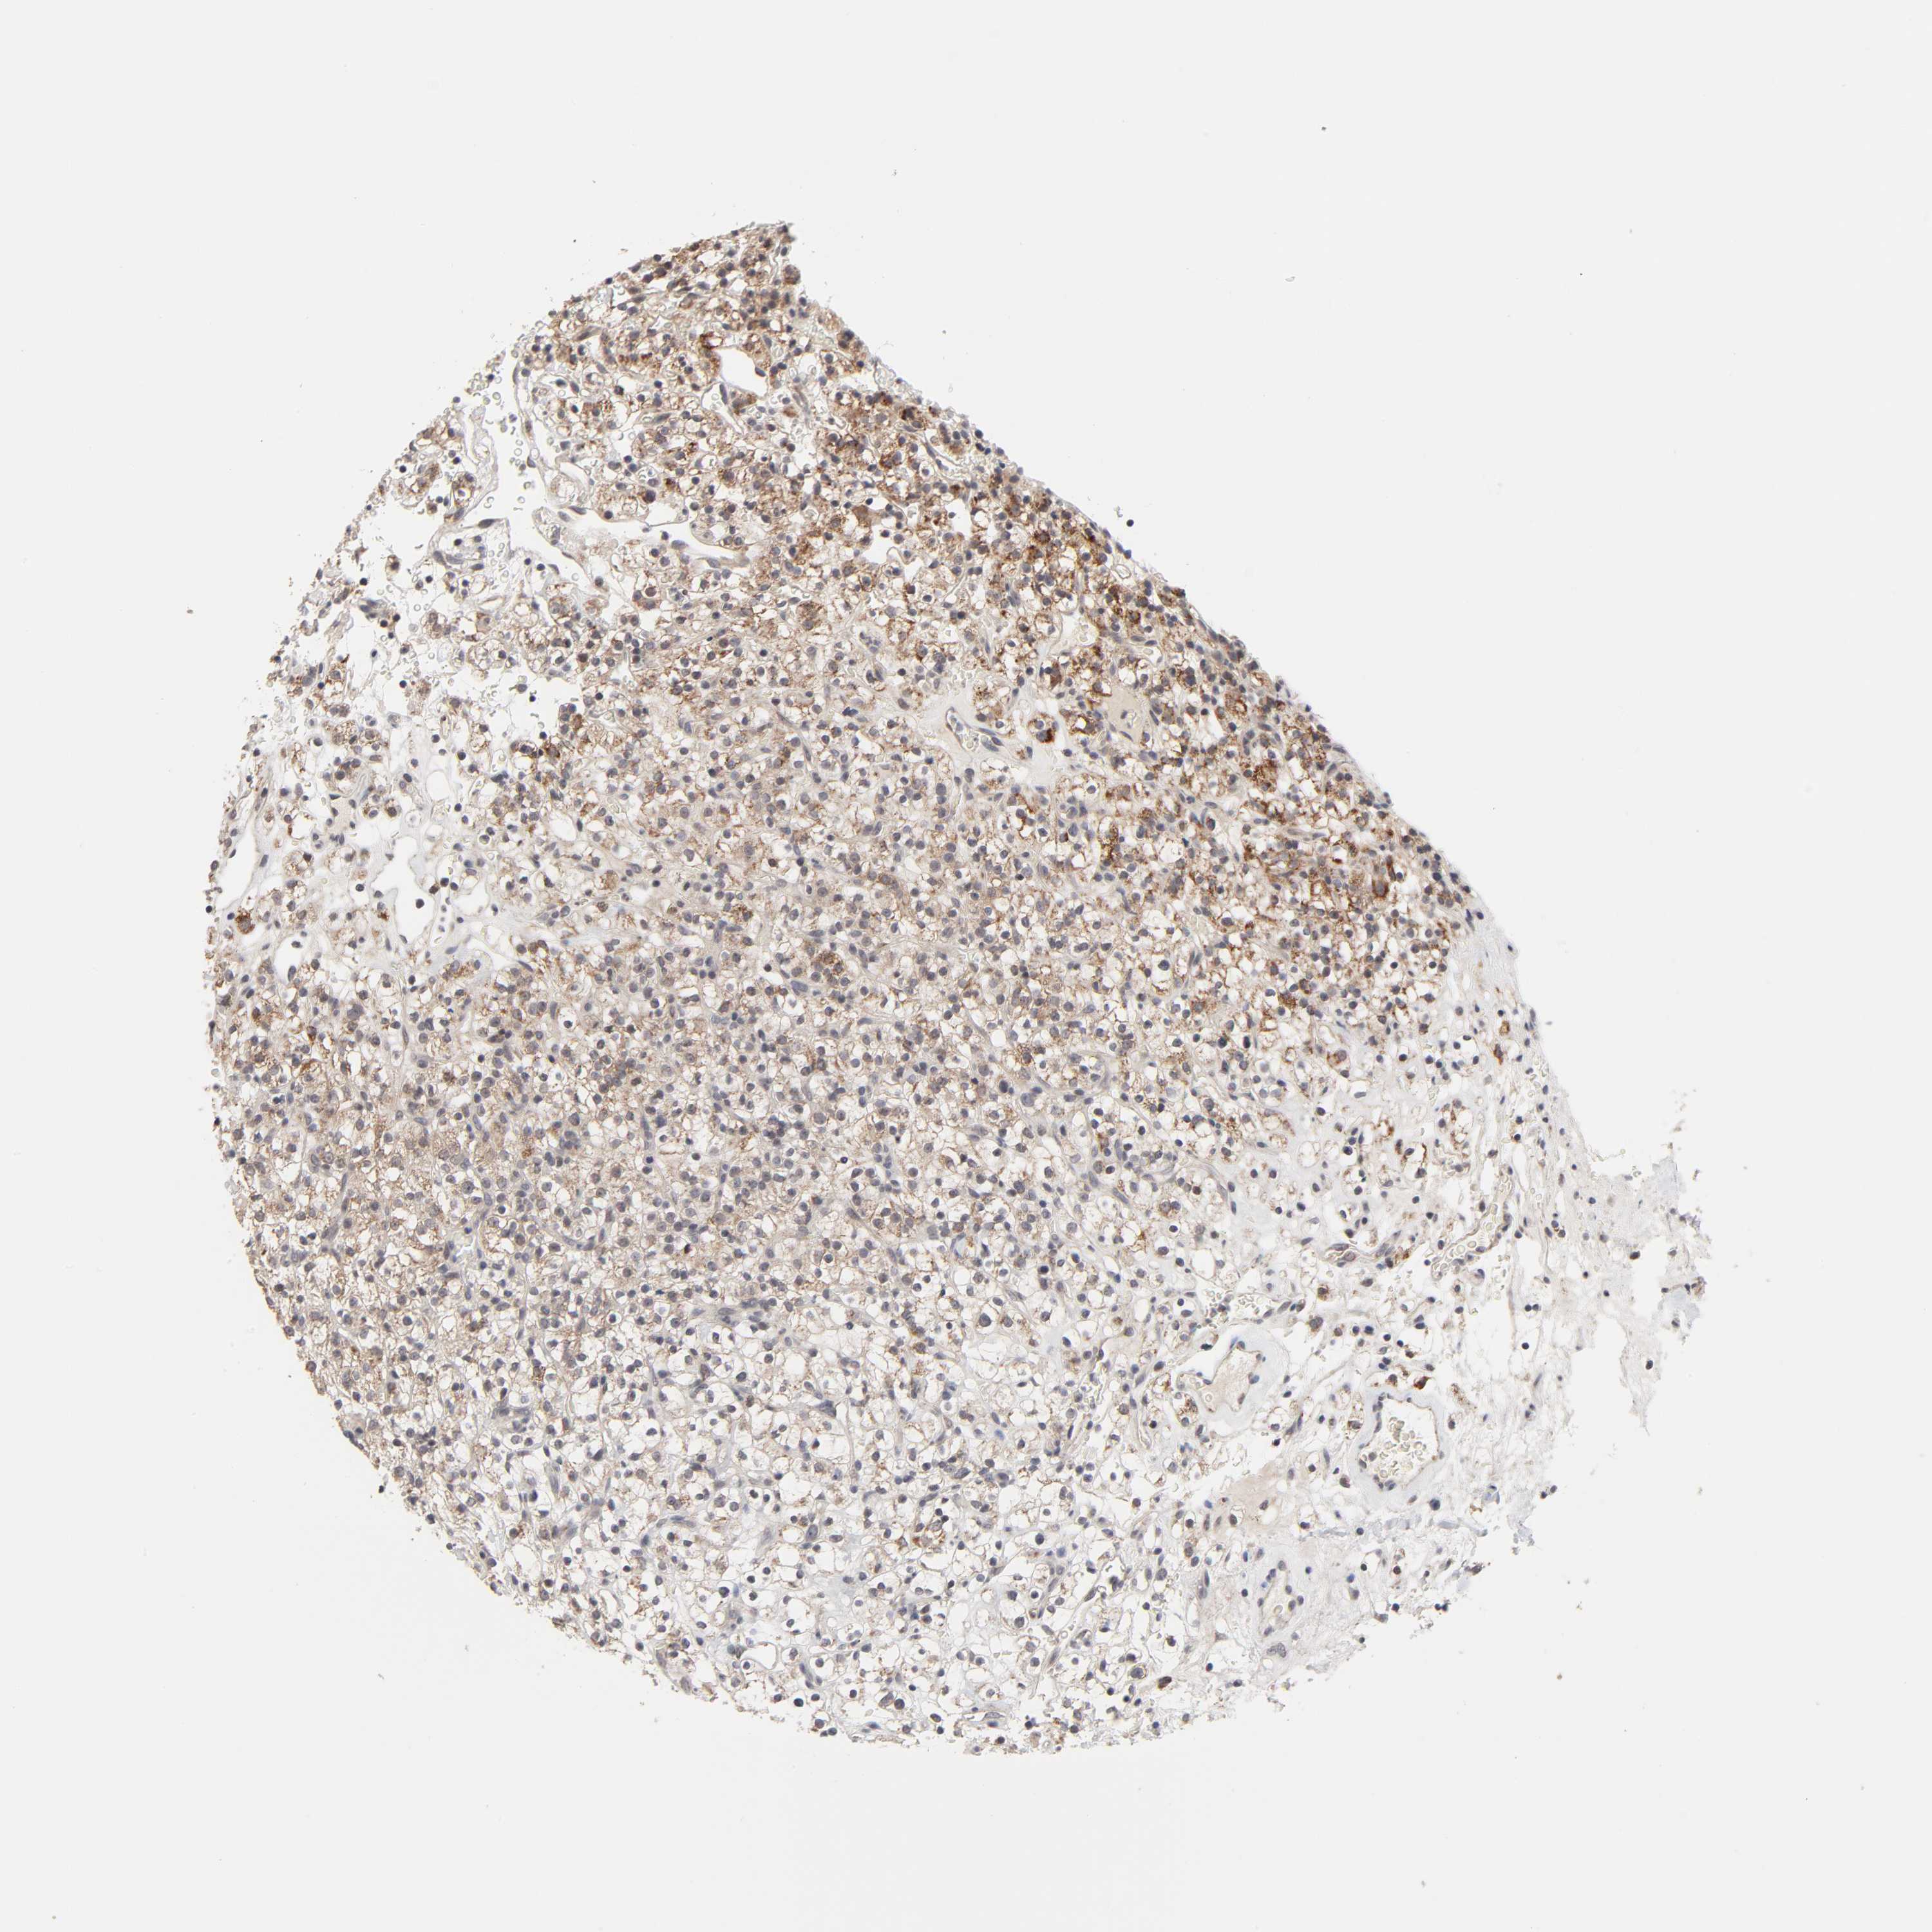

KIDNEY RENAL CLEAR CELL CARCINOMA (VALIDATION) - Interactive survival scatter ploti

The Survival Scatter plot shows the clinical status (i.e. dead or alive) for all individuals in the patient cohort, based on the same data that underlies the corresponding Kaplan-Meier plots. Patients that are alive at last time for follow-up are shown in blue and patients who have died during the study are shown in red.

The x-axis shows the expression levels (FPKM) of the investigated gene in the tumor tissue at the time of diagnosis. The y-axis shows the follow-up time after diagnosis (years). Both axes are complimented with kernel density curves demonstrating the data density over the axes. The top density plot shows the expression levels (FPKM) distribution among dead (red) and alive patients (blue). The right density plot shows the data density of the survived years of dead patients with high and low expression levels respectively, stratified using the cutoff indicated by the vertical dashed line through the Survival Scatter plot. This cutoff is automatically defined based on the FPKM cutoff that minimizes the p-score. The cutoff can be changed by dragging the vertical line or by entering a cutoff value in the square labeled "Current cut-off".

Under the Survival Scatter plot the p-score landscape (black curve; left axis) is shown together with dead median separation (red curve; right axis). Dead median separation is the difference in median mRNA expression between patients who have died with high and low expression, respectively. It is calculated as follows: median FPKM expression of dead patients with high expression - median FPKM expression of dead patients with low expression. This is intended to aid the user in visually exploring custom cutoffs and the associated p-scores and dead median separation.

Individual patient data is displayed and can be filtered by clicking on one or more of the category buttons on the top of the page. Categories describing expression level and patient information include: high, low, alive, dead, female, male and tumor stages. The scale of the x-axis can be toggled between linear and log-scale by clicking on the "x log" button. Mouse-over function shows TCGA ID, patient information and mRNA expression (FPKM) for each patient.

& Survival analysisi

Kaplan-Meier plots summarize results from analysis of correlation between mRNA expression level and patient survival. Patients were divided based on level of expression into one of the two groups "low" (under cut off) or "high" (over cut off). X-axis shows time for survival (years) and y-axis shows the probability of survival, where 1.0 corresponds to 100 percent.

AUH is validated prognostic, high expression is favorable in Kidney Renal Clear Cell Carcinoma (validation)

: 19.47

Average pTPM 29.4

Number of samples 100